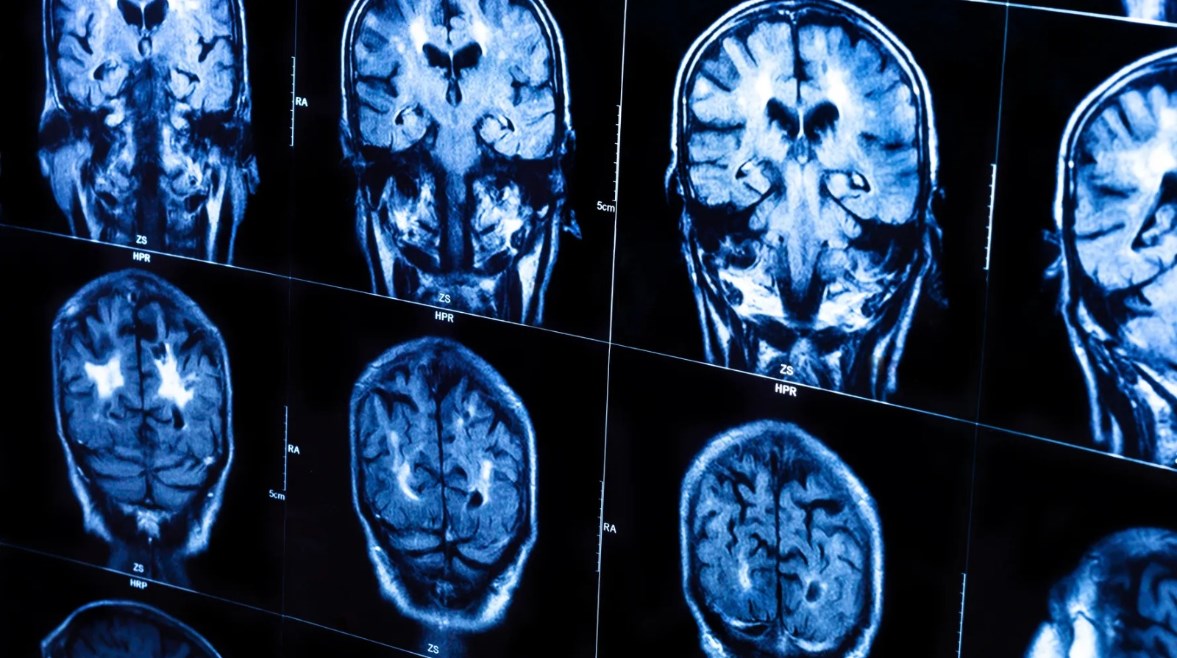

دراسة جديدة توضح لماذا تعمل أدمغة الذكور بشكل مختلف بيولوجيًا عن الإناث؟

منذ عقود تناقش اختلاف السلوكيات والذكاء بين النساء والرجال، وإلى الآن تستمر المناقشات حول هذه الاختلافات، إذ تظهر مجموعة متزايدة من الأدلة العلمية أن مئات الجينات تعمل بشكل مختلف في أدمغة البشر الذكور أو الإناث بيولوجيًا.

وأكدت عقود من الأبحاث وجود اختلافات بين الرجال والنساء في بنية الدماغ ووظيفته وقابليته للإصابة بالاضطرابات العقلية، ويمكن قياس تأثير هذه العوامل الوراثية من خلال النظر مباشرةً إلى نشاط الجينات في أدمغة الرجال والنساء.

وكشفت دراسة أخرى أجريت على النسخ الجينية في الدماغ عن وجود 610 جينات أكثر نشاطا في أدمغة الذكور، و316 جينًا أكثر نشاطًا في أدمغة الإناث.

في دراسة جديدة أُجريت عام 2025، فحصت 266 دماغًا لأجنة بعد الوفاة، ووجدت أن أكثر من 1800 جين كانت أكثر نشاطًا لدى الذكور و1300 لدى الإناث، وتداخلت هذه المجموعات من الجينات المتحيزة جنسيًا مع تلك الموجودة في أدمغة البالغين، ويشير هذا إلى التأثيرات الجينية المباشرة للجينات على الكروموسومات الجنسية، وليس إلى الاختلافات الناجمة عن الهرمونات.